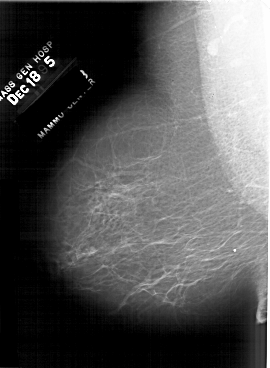

A_1633_1.LEFT_CC

LEFT_CC LINES 6406 PIXELS_PER_LINE 4201 BITS_PER_PIXEL 12 RESOLUTION 43.5 NON_OVERLAY